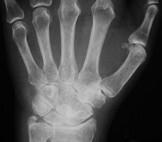

问题 女,56岁,手指关节肿胀,疼痛,僵硬,结合影像图像,选择最可能的诊断 ( )

选项 A、Reiter综合征 B、骨囊肿 C、类风湿关节炎 D、痛风性关节炎 E、关节结核

答案 C